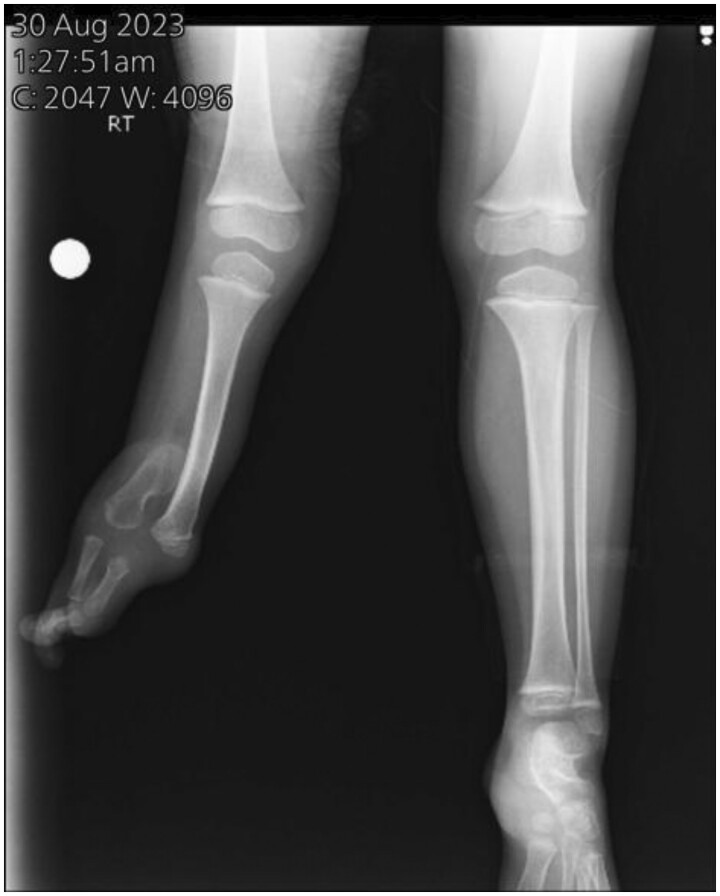

Fibular hemimelia (FH) is a rare congenital abnormality where the fibula is either totally or partially absent. It can occur alone or alongside other skeletal malformations, and in very few cases, it may occur along with non-skeletal anomalies. A 4-year-old female was diagnosed with unilateral right-sided FH, accompanied by limb shortening, a right-side ankle deformity, valgus foot, and 3 lateral rays that had been totally absent since the first week of birth. And she was incidentally diagnosed with spina bifida occulta at a 3-year-old age. FH is most commonly unilateral and mostly affects the right side, leads to a limb-length discrepancy, and maybe comes as a symptom of a syndrome such as Foetus-Fibula-Ulna syndrome and so on. Risk factors include prenatal history, drugs, and no supplementation intake. Together, these elements could be a contributing factor to our condition. The congenital limb abnormalities may be discovered during pregnancy by sonography. If present, other investigations need to be done to differentiate the diagnosis. Treatment according to degree: mild, moderate, and severe cases. In our case, the type 2 FH characteristic was shown by sonography, accompanied by limb shortening, lateral rays absent, and a non-skeletal anomaly (spina bifida). These anomalies very rarely come with each other at the same time. To the best of our knowledge, this case is exceptional in that FH is present at birth alongside spina bifida.